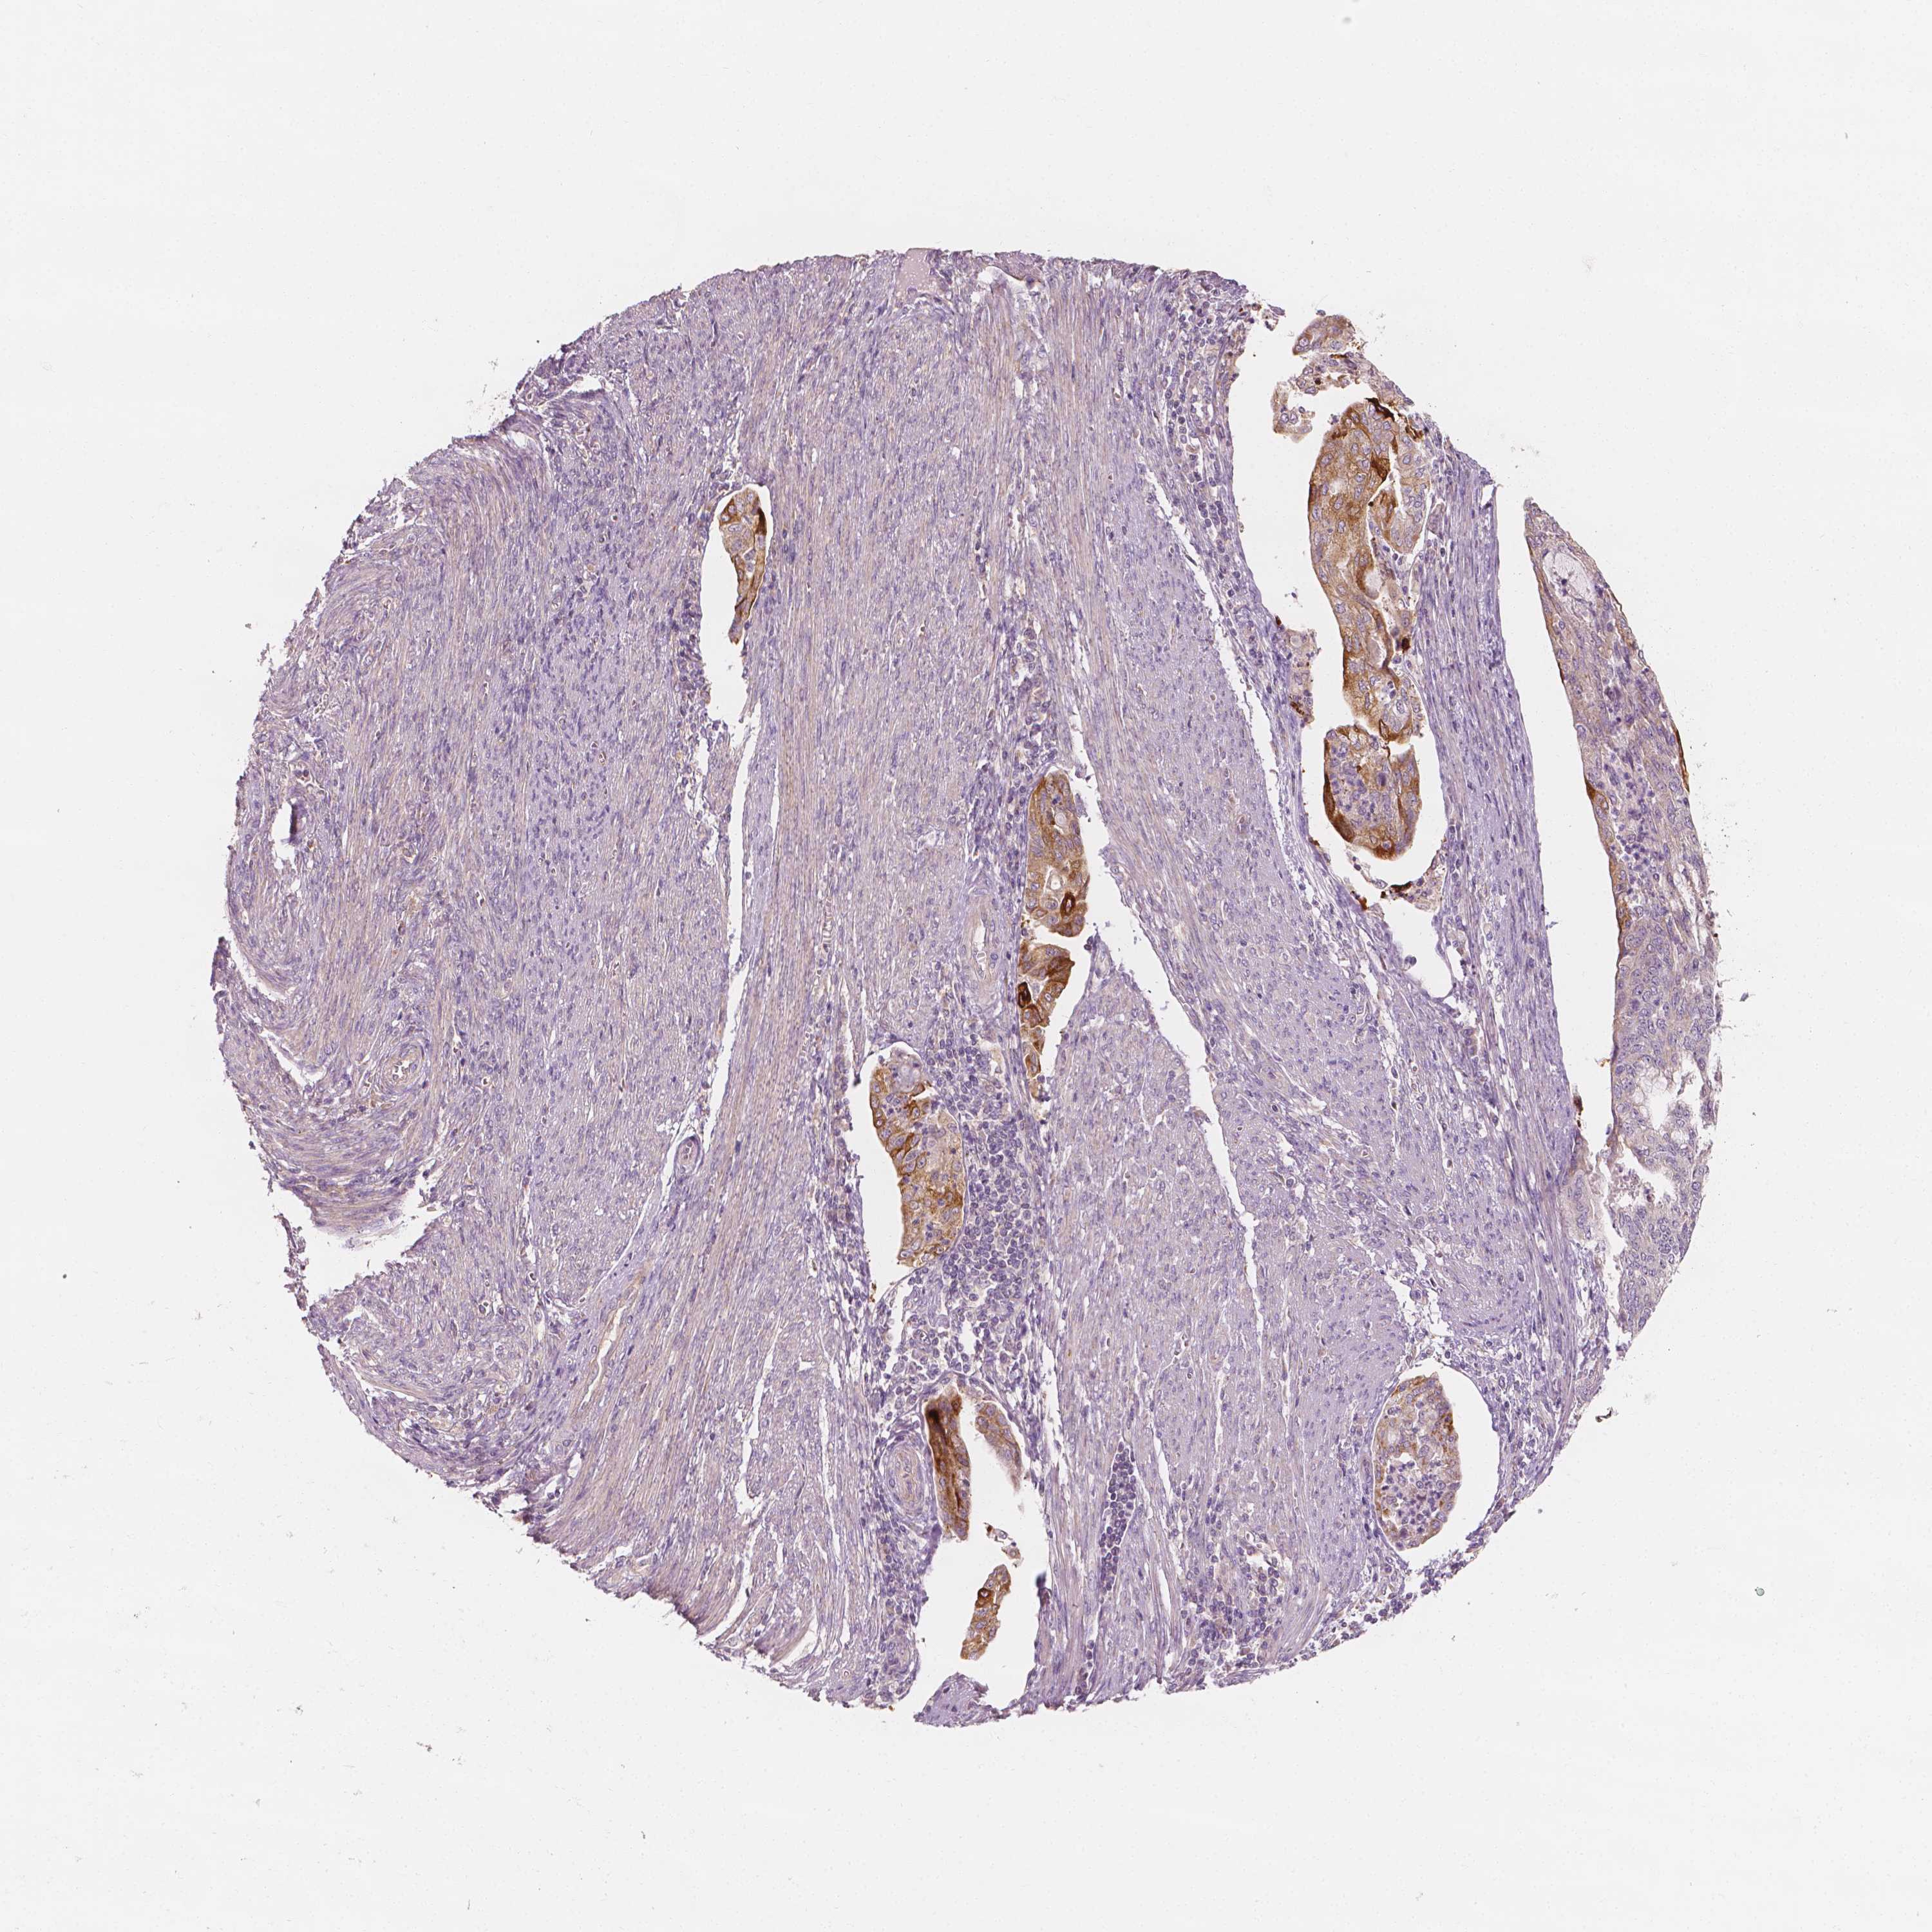

ENDOMETRIAL CANCER - Protein expressioni

A mouse-over function shows sample information and annotation data. Click on an image to view it in a full screen mode. Samples can be filtered based on level of antibody staining by selecting one or several of the following categories: high, medium, low and not detected. The assay and annotation is described here.

Note that samples used for immunohistochemistry by the Human Protein Atlas do not correspond to samples in the TCGA dataset.

Antibody stainingi

Antibody staining in the annotated cell types in the current human tissue is reported as not detected, low, medium, or high, based on conventional immunohistochemistry profiling in selected tissues. This score is based on the combination of the staining intensity and fraction of stained cells.

Each image is clickable and will lead to virtual microscopy that enables deeper exploration of all samples and also displays staining intensity scores, fraction scores and subcellular localization as well as patient and tissue information for each sample.

Antibody HPA024361

Antibody HPA064939

Staining

High

Medium

Low

Not detected

Intensity

Strong

Moderate

Weak

Negative

Quantity

>75%

75%-25%

<25%

None

Location

Nuclear

Cytoplasmic/membranous

Cytoplasmic/membranous,nuclear